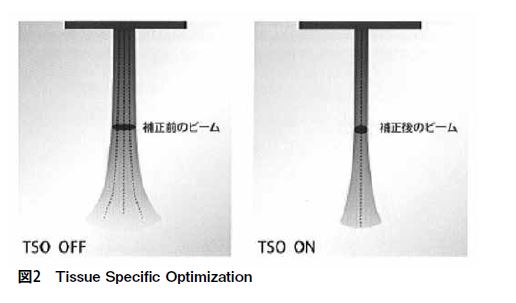

Aplio500には、生体内での音速のばらつきにより、方位分解能が劣化する場合にばらつきを補正して、画質劣化を改善するTissue Specific Optimizationという機能がある。複数の音速で計算を行い、コントラスト比が最も高くなるよう音速を推定して設定することで、画質の劣化を防ぐ機能である(図2)。